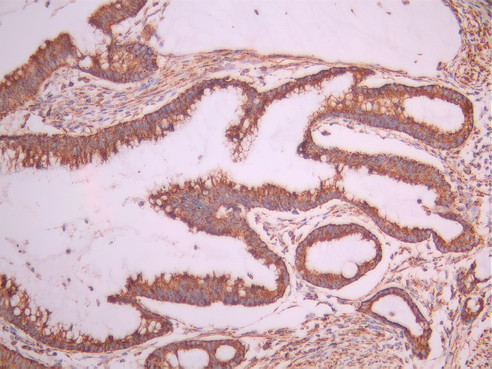

IHC image of CSB-RA208703A0HU diluted at 1:100 and staining in paraffin-embedded human gastric cancer performed on a Leica BondTM system. After dewaxing and hydration, antigen retrieval was mediated by high pressure in a citrate buffer (pH 6.0). Section was blocked with 10% normal goat serum 30min at RT. Then primary antibody (1% BSA) was incubated at 4°C overnight. The primary is detected by a Goat anti-rabbit polymer IgG labeled by HRP and visualized using 0.05% DAB.